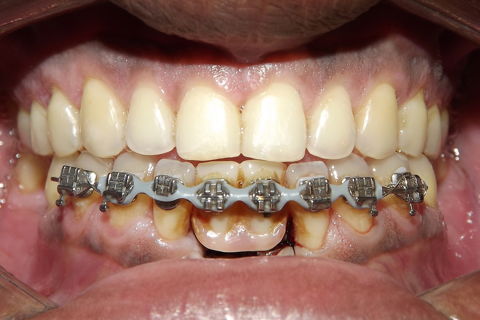

fotos iniciais do caso.

Paciente do sexo masculino, 36 anos, brauifacial. Relatava que os Diastemas lhe incomodavam muito, e em tratamento anterior o profissional fez exo de 2 incisivos centrais inferiores e instalou Prótese movel com 4 incisivos, após um tempo de uso a prótese começou a incomodar. em planejamento com o implantodontista ficou definido o fechamento dos diastemas e reabilitação dos elementos 41 e 31 com implantes.

segue as fotos do caso